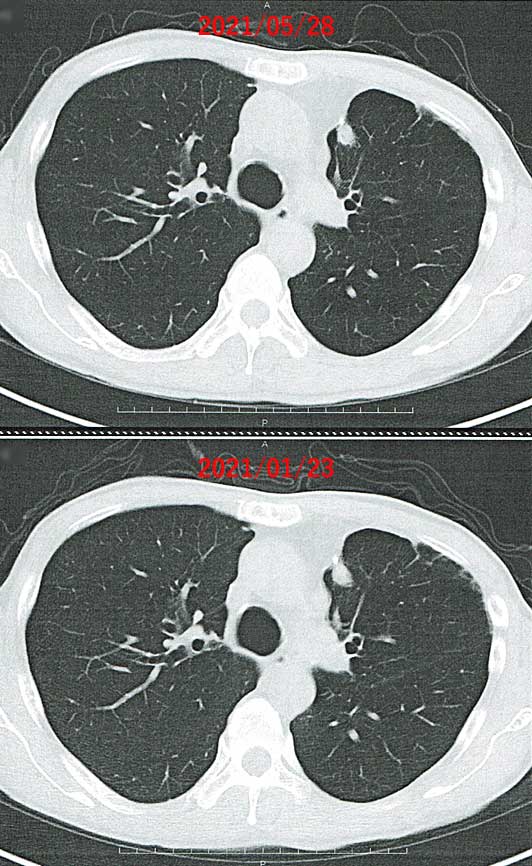

| 2021年6月8日(火) |

東邦大学医療センター大森病院にて、血液検査と尿検査を実施し、呼吸器内科の診察を受けて、外来化学療法室でアバスチンの投与を受けました。 血液検査、尿検査ともに異常無しです。 5月28日に撮ったCTも異常無しです。むしろ、改善が見られました。 右肺の腫瘍は、放射線治療後も色が薄くなったとはいえ、影が写っていました。医師からは「おそらく、死んでいるか、非活性化していると思いますが、念のため、大きくならないか観察していきましょう」と言われていましたが、それがすっかり消えて無くなっています。※5月28日の画像の広く大きい白い影は放射線による「やけど」の痕で、がん細胞ではありません。

左肺の腫瘍も、若干小さくなっているように見えます。

医師は「進行していなければ良いので、良い状態です」と満足そうです。 最近治療として行っているのは、以下の3つだけです。